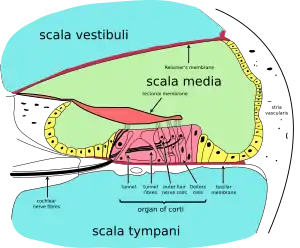

- the cochlear duct or scala media (containing endolymph) a region of high potassium ion concentration that the stereocilia of the hair cells project into

- Reissner's membrane, which separates the vestibular duct from the cochlear duct

- The basilar membrane, a main structural element that separates the cochlear duct from the tympanic duct and determines the mechanical wave propagation properties of the cochlear partition

- The Organ of Corti, the sensory epithelium, a cellular layer on the basilar membrane, in which sensory hair cells are powered by the potential difference between the perilymph and the endolymph

- hair cells, sensory cells in the Organ of Corti, topped with hair-like structures called stereocilia

The walls of the hollow cochlea are made of bone, with a thin, delicate lining of epithelial tissue. This coiled tube is divided through most of its length by an inner membranous partition. Two fluid-filled outer spaces (ducts or scalae) are formed by this dividing membrane. At the top of the snailshell-like coiling tubes, there is a reversal of the direction of the fluid, thus changing the vestibular duct to the tympanic duct. This area is called the helicotrema. This continuation at the helicotrema allows fluid being pushed into the vestibular duct by the oval window to move back out via movement in the tympanic duct and deflection of the round window; since the fluid is nearly incompressible and the bony walls are rigid, it is essential for the conserved fluid volume to exit somewhere.

The lengthwise partition that divides most of the cochlea is itself a fluid-filled tube, the third 'duct'. This central column is called the cochlear duct. Its fluid, endolymph, also contains electrolytes and proteins, but is chemically quite different from perilymph. Whereas the perilymph is rich in sodium ions, the endolymph is rich in potassium ions, which produces an ionic, electrical potential.

The hair cells are arranged in four rows in the Organ of Corti along the entire length of the cochlear coil. Three rows consist of outer hair cells (OHCs) and one row consists of inner hair cells (IHCs). The inner hair cells provide the main neural output of the cochlea. The outer hair cells, instead, mainly 'receive' neural input from the brain, which influences their motility as part of the cochlea's mechanical "pre-amplifier". The input to the OHC is from the olivary body via the medial olivocochlear bundle.

The cochlear duct is almost as complex on its own as the ear itself. The cochlear duct is bounded on three sides by the basilar membrane, the stria vascularis, and Reissner's membrane. The stria vascularis is a rich bed of capillaries and secretory cells; Reissner's membrane is a thin membrane that separates endolymph from perilymph; and the basilar membrane is a mechanically somewhat stiff membrane, supporting the receptor organ for hearing, the Organ of Corti, and determines the mechanical wave propagation properties of the cochlear system.